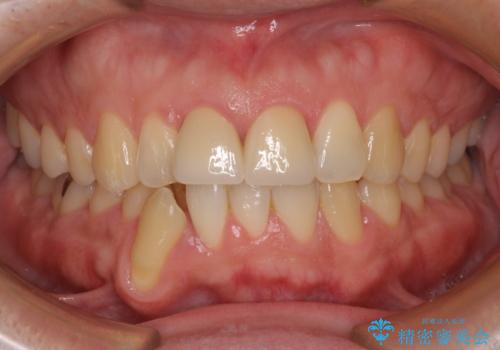

失活した歯は、根管治療を行った後に部分矯正により歯根を引っ張り出し、歯周外科処置により左右の歯肉の位置が揃えることとしました。

強い衝撃を受けた歯であるため、定期的にレントゲン撮影を行い、歯根吸収が起きていたり、神経が失活していたりしないか確認を行い、ある程度安定したところでオールセラミッククラウンにて補綴治療を行うこととしました。

歯をぶつけてから1年後のレントゲン写真を取りましたが、どちらの歯も大きな異常は認められませんでした。

今後も定期的にレントゲン写真による経過観察が必要となります。